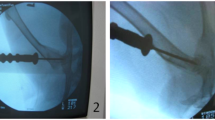

Furthermore, we commonly observed low-density shadows on CT scans inBME group. The presence of these low-density areas on CT scans typically signals extensive bone destruction and marked reduction in bone mass within those specific regions. To further investigate this observation, we conducted a quantitative assessment to determine the ratio of low-density areas to the entire volume of the femoral head. Our findings notably demonstrated that the prevalence of low-density regions was considerably greater in the BME group when compared to the control group (Fig. 3A-B).

Analysis of CT low-density area between BME and control groups. (A) CT and MRI imaging of typical case. Green circles represented the area of the femoral head, while red regions indicated the area of low-density shadows on the CT scan. (B) Quantification of CT low-density area ratio. n = 25 for each group, ***p < 0.001.